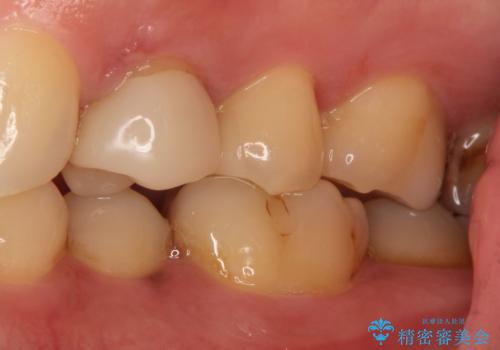

セラミックインレーで治療しました。

- 154,000円(77,000×2)費用は治療当時の料金となります

以前保険治療で治したところが再び虫歯になっていました。保険治療で使用される材料は主にプラスチックなので必ず劣化がおきます。再治療のリスクを減らすために、セラッミックインレーで治療を行いました。セラミックインレーには劣化がほとんどありません。当院ではシリコンで型取りを行っているので、適合が良い被せものが出来き再治療のリスクを減らすことが出来ます。